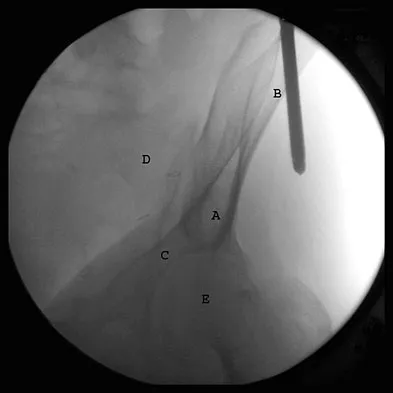

Question 18

The correct starting point for an external fixation half pin placed into the anterior inferior iliac spine (AIIS) is labeled by what letter in Figure 3?